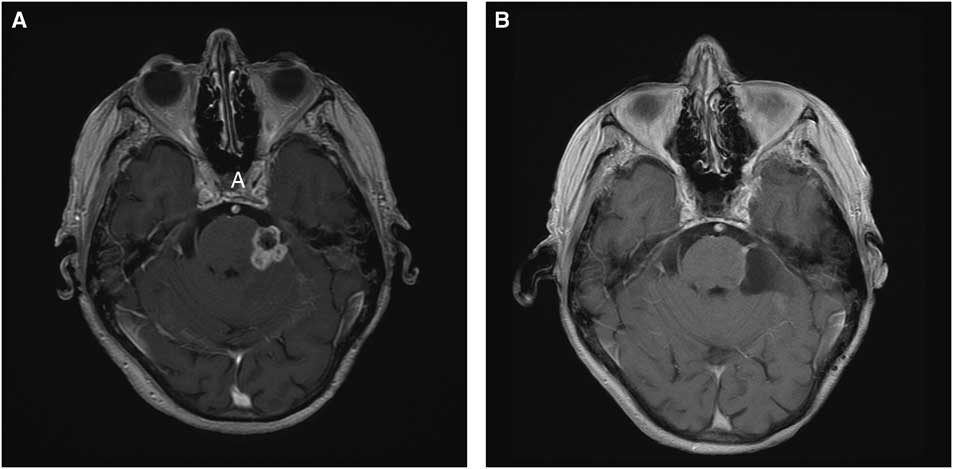

We report a case of a 77-year-old female with remote history of breast cancer and mastectomy who was referred to our center for evaluation and treatment of an unusual mass lesion located in the posterior fossa (Figure 1). She had an onset of trigeminal neuralgia beginning in 2000 for which she underwent a microvascular decompression in 2006; a shredded Teflon felt implant was placed between the culprit superior cerebellar artery and the underlying trigeminal nerve root. Of note, we occasionally use fibrin glue in conjunction with the shredded Teflon implant; however, this was not used in this case and not used routinely. She received limited pain relief and in 2007 underwent a Gamma Knife procedure in which an 80-Gy dose was prescribed to the proximal trigeminal nerve root. Neither computed tomography nor magnetic resonance imaging demonstrated any abnormality aside from the Teflon implant. She experienced minimal, delayed pain relief, and continued with medical management until undergoing radiofrequency rhizotomy in 2009, which provided minimal pain relief. This also resulted in corneal anesthesias and 80% preservation of sensation in V1 and V2 distributions and full preservation of V3. Over the ensuing years, she developed a progressive full sensory loss of all three trigeminal nerve distributions, temporalis and masseter muscle atrophy, accompanied by alleviation of her neuralgia. In 2015, she developed a progressive gait ataxia with magnetic resonance imaging revealing a lobulated, enhancing 2.2×1.8×1.6 cm mass in the region of the previously inserted Teflon implant along with significant edema involving adjacent brain.

Figure 1 Panel A: Pre-operative Axial MRI with Gadolinium shows a 2.2×1.8×1.6 cm enhancing legion at the site of the trigeminal root entry zone. Panel B: Post-operative Gadolinium enhanced axial sequence showing minimal residual enhancing lesion.

Based on the clinical presentation and imaging findings, the differential diagnosis included metastasis, meningioma, chronic infectious process involving Teflon implant, inflammatory or granulomatous lesion, and radiation-induced pathology. Given her progressive gait ataxia along with unknown diagnosis, we elected to proceed with posterior fossa exploration through a retrosigmoid craniectomy with the goal of alleviation of mass effect and tissue sampling for diagnosis. The lesion was noted to have a firm capsule surrounding the inner contents of the tumor, consisting of soft white material intermixed with the Teflon implants. The lesion was adherent to the cerebellum, pons, trigeminal root entry zone, and superior cerebellar artery. After internal debulking and meticulous dissection of the tumor from the neurovascular structures, a thin rim of residual tumor was left adherent to the nerve and superior cerebellar artery.